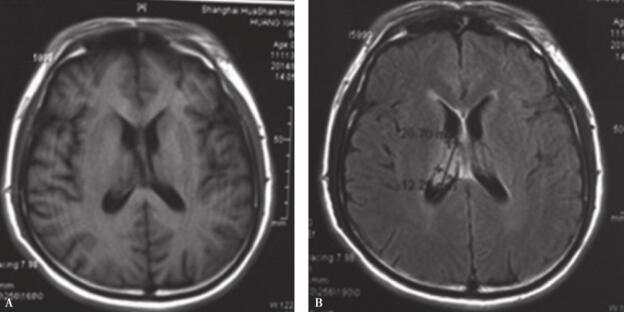

患者,男性,44岁。警察职业。今年3月份以来出现双下肢乏力,7月份出现反复头痛,8月中旬出现伴意识模糊。头颅CT及MRI提示颅内多发病变,右侧侧脑室结节样病变(图1,图2)。按“感染性肉芽肿”予抗感染治疗,患者症状有一定改善,仍有反应迟钝。转入我科治疗。

图1 右侧脑室体部结节病灶

A.头颅 MRI平扫 T1 ;B.头颅 MRI FLAIR 像;C.头颅 MRI DWI;D.头颅 MRI T1 增强